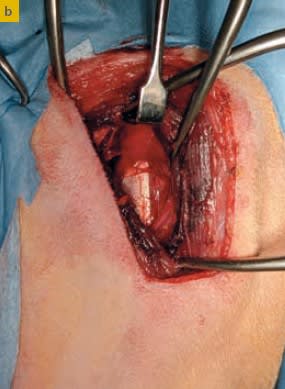

Editorial :  Edra. Miguel Solano Nicolás, Felipe de Vicente Collado, Alan Danielski, Stephen Kalff . 168 páginas . tapa dura. Ortopedia en pequeños animales. El miembro anterior se ha concebido como una obra práctica en la que se describen con detalle las técnicas quirúrgicas existentes, comunes y complejas, de las patologías más frecuentes del miembro anterior de perros y gatos, incluyendo desde la planificación de las intervenciones al posoperatorio. Los contenidos se acompañan de imágenes de gran calidad y más de 20 vídeos.